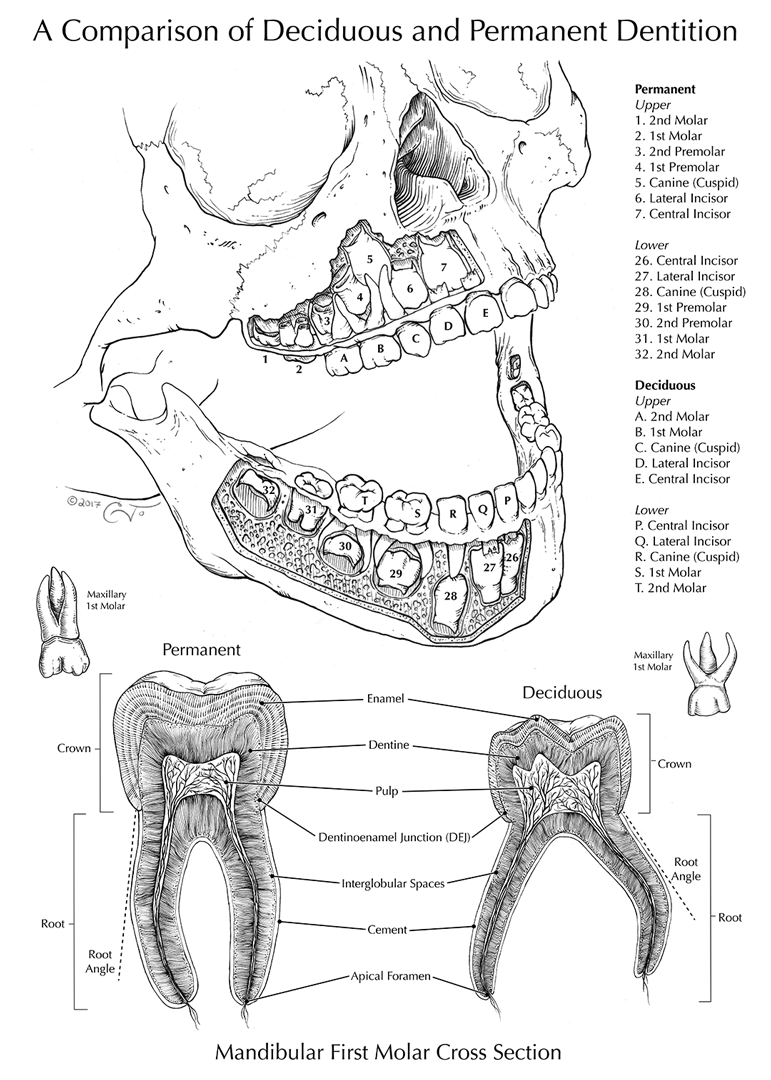

- Anatomy illustration translation from tone

- Anatomy illustration (from cadaver dissection)

Student Artwork